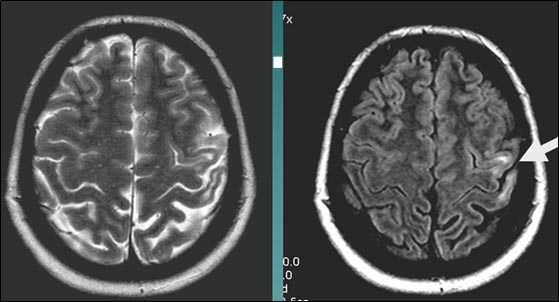

Внутримозговая гематома правой теменной доли. Граница поздней подострой и ранней хронической стадии. В Т2-ВИ виден ободок гемосидерина (стрелка).

Хочется подчеркнуть возможность МРТ в выявлении последствий геморрагического поражения - остается хорошо дифференцируемый по Т2 ободок гемосидерина, недоступный для визуализации при других методах нейровизуализации.

Стрелками показан ободок гемосидерина по периферии постишемической кисты.